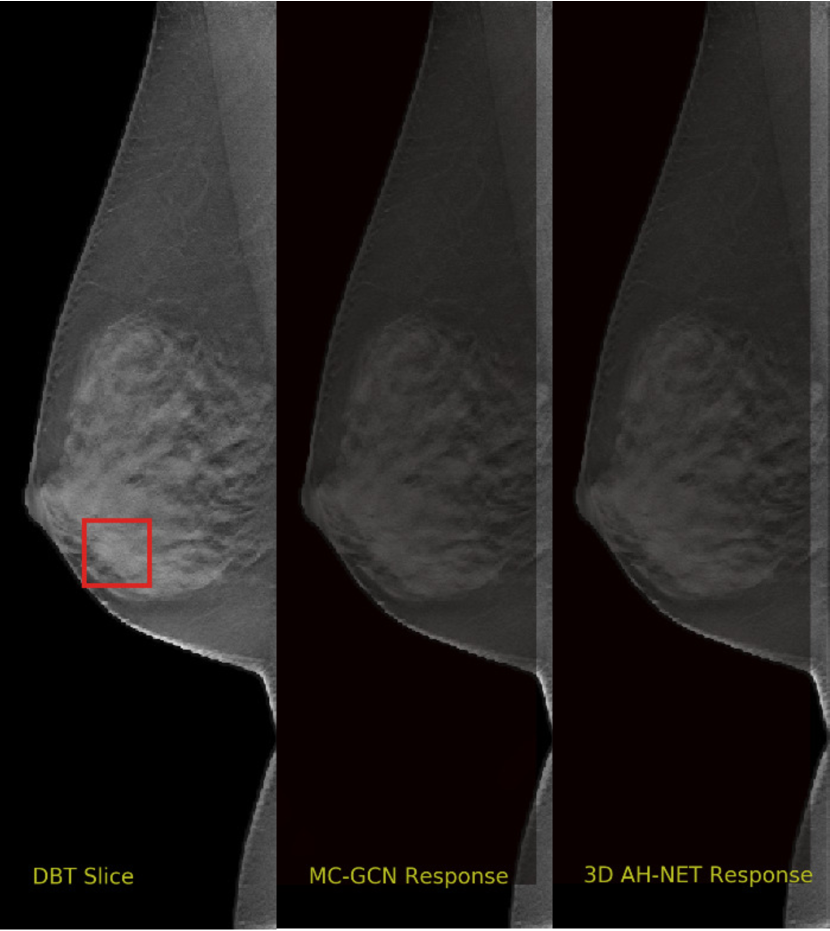

We selected some example slices from the DBT dataset to demonstrate the advantage of our proposed AH-Net for the Breast cancer screening. From Fig. 8 to Fig. 12, we show slices from five test DBT volumes that both the MC-GCN and the proposed 3D AH-Net could successfully detect the suspected breast lesion. The original DBT slice is shown on the left with the lesion annotated by our radiologist. Please note the original annotation is a 3D box. The figures in the middle and on the right are response maps from MC-GCN and 3D AH-Net overlaid on the original image, respectively. The detection locations obtained with non-maximal suppression are displayed with cross markers. As shown in the images, the proposed network can detect breast lesions varying in sizes and appearances. The confidence of the 3D AH-Net is usually higher than that of MC-GCN. From Fig. 13 to Fig. 17, we show five volumes that MC-GCN failed to detect the lesions since the lesions were not distinguishable from other breast tissues using the information within the slice. In contrast, 3D AH-Net was able to detect the lesions from such volumes using the 3D context between slices. As shown in Fig. 18 to Fig. 22, there are also volumes with lesions that both network failed to detect. Such lesions normally reside in the dense breast tissues. The boundary between these lesions and the normal breast tissues usually have low contrast. The networks sometimes also confuse them with other roundish structures in the breast such as lymph nodes or skin moles.

Refer to caption

Figure 8: Example DBT slice 1 with a lesion that can be detected by both MC-GCN and 3D AH-Net. Though the lesion is blended in the dense breast tissues, our network is able to detect it according to the speculations around the lesion boundary.

Figure 9: Example DBT slice 2 with a lesion that can be detected by both MC-GCN and 3D AH-Net. The lesion is small and can also be identified with the architectural distortion in the surrounding tissues.